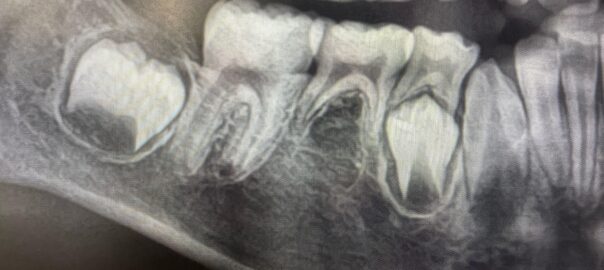

- 2025年9月13日 根っこの再治療

こんにちは、静岡市清水区川原町のわたなべミント歯科です。 今回は、歯の根っこの先に膿がたまったりして、病巣ができてしまった時に行う、感染根管処置という治療についてお話ししたいと思います。 主に神経を取った歯に起こりやすい … 続きを読む 根っこの再治療